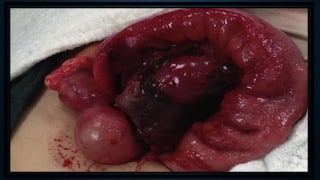

• El exudado fibrinoso inicial produce la adherencia

de epiplón y de las asas delgadas adyacentes, a

manera de mecanismo de defensa que intentará

bloquear el proceso para impedir una peritonitis

generalizada. Esto se denomina PLASTRÓN

APENDICULAR.

• Cuando la perforación se lleva a cabo dentro de un

plastrón y el proceso inflamatorio e infeccioso

dentro del plastrón digieren el apédice y producen

pus, hablamos de lo que se denomina ABSCESO